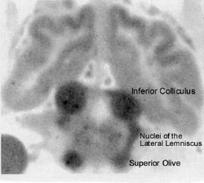

Note: Cardiac gating by the method of Guimaraes et al.

(1998) will be used; the high rate of blood flow in the

brainstem causes pulsations that mask most auditory

stimuli.  Quiet MRI as described by Yetkin et al. (2004) will

also be employed.  The highest rate of blood flow is to the

inferior colliculi, as was revealed in the experiments on

cerebral circulation by Landau et al. (1955) in radiographic

pictures as shown to the right.

From Kety (1962)on research of

Landau et al. (1955) Trans Am

Neurol Assoc 80:125-9.